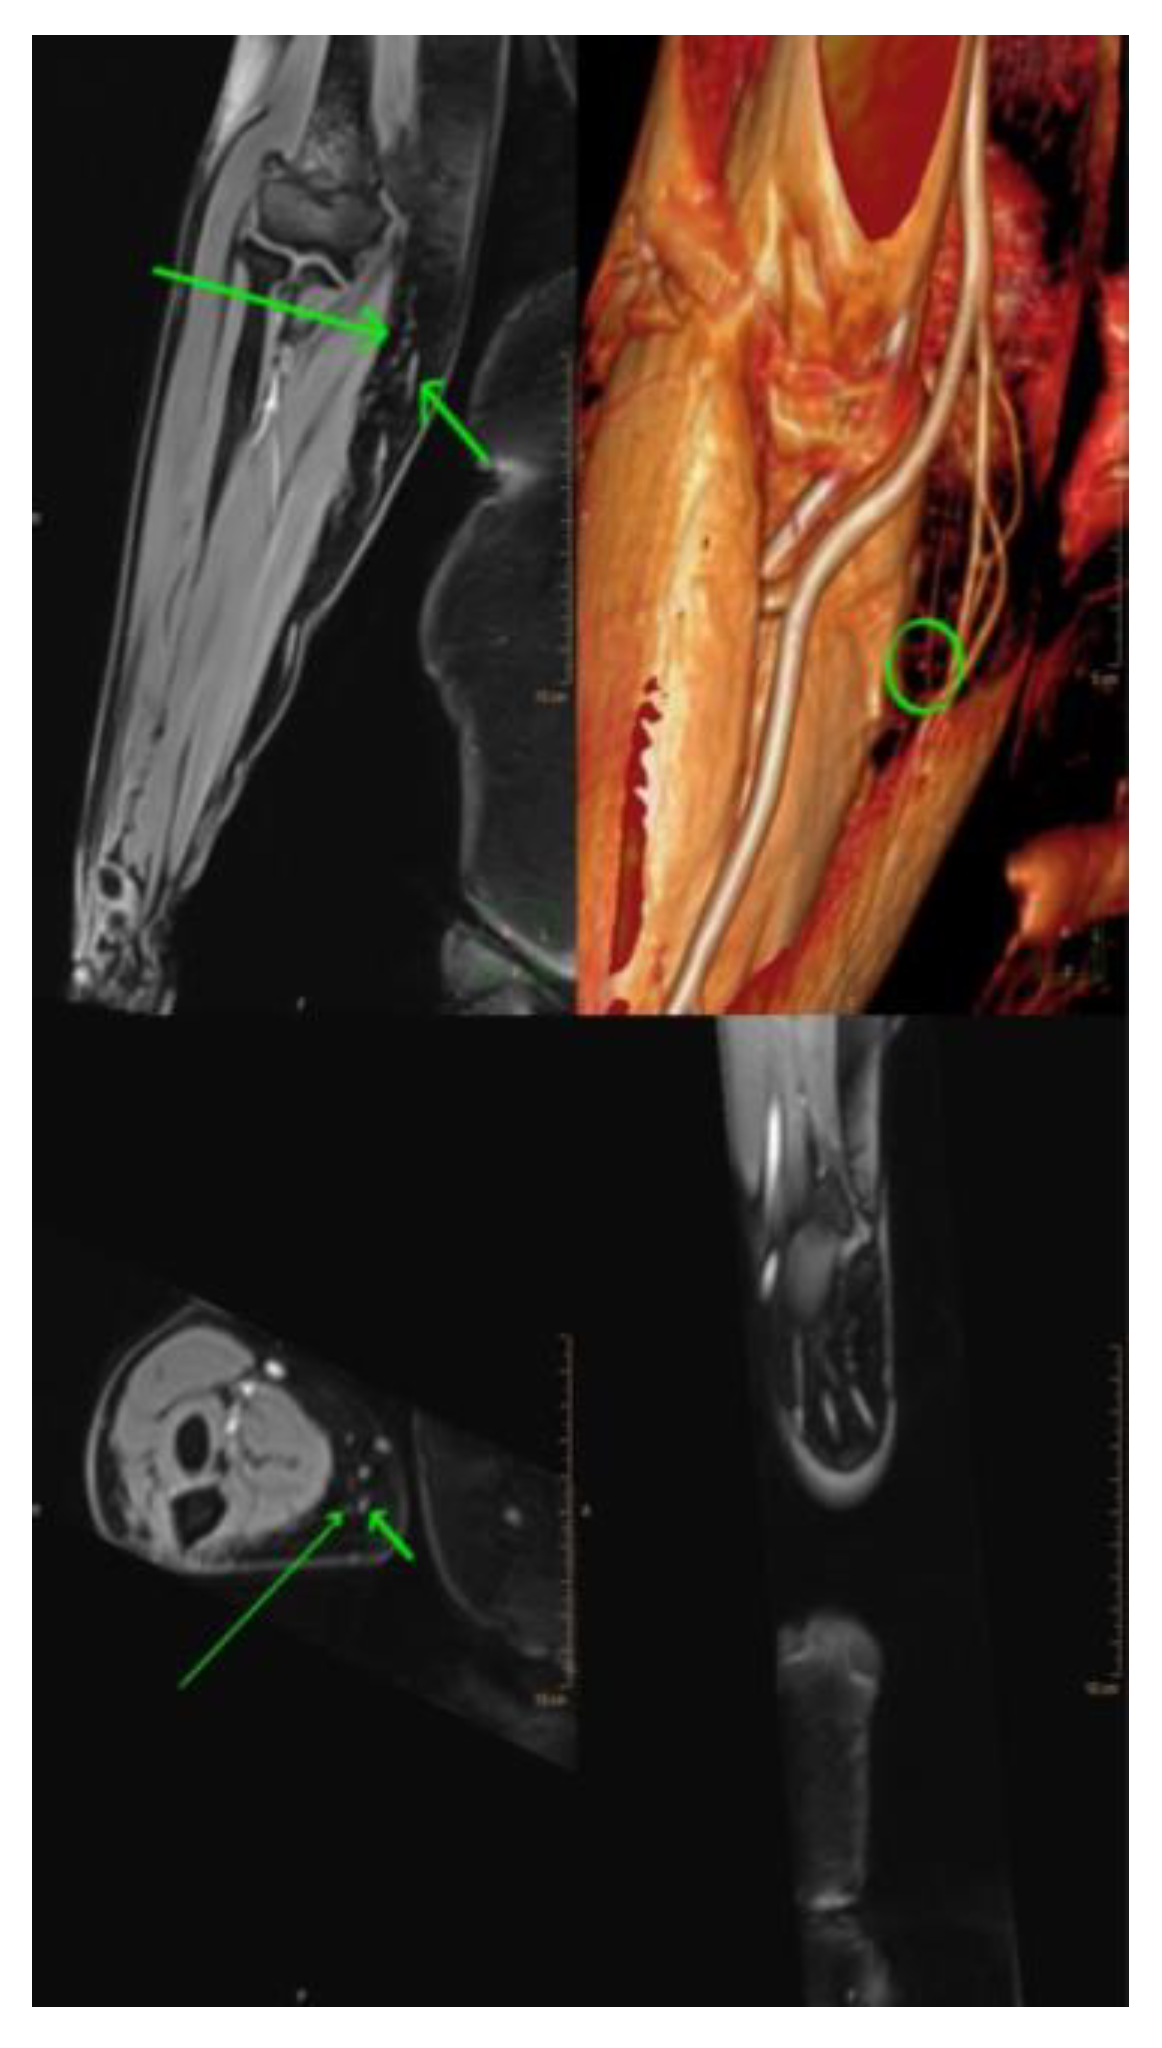

3.2. Magnetic resonance lymphangiography (MRL)